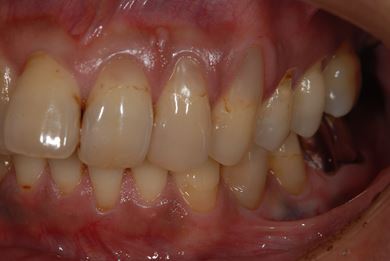

インプラントの症例写真 IMPLANT

インプラント治療+セラミック治療

| 性別/年齢 | 男性 / 36歳 | ||||||||||||||||||||||||||||||||

| 主訴 | インプラント治療と、その他全体的に歯の治療を希望。 | ||||||||||||||||||||||||||||||||

| 治療方針 | 欠損部分をインプラント治療にて、機能的・審美的回復を行う。 | ||||||||||||||||||||||||||||||||

| 治療内容 | インプラント2本、メタルボンドセラミッククラウン3本(メタルボンド用土台1本) | ||||||||||||||||||||||||||||||||

| 総治療費 | 629,685円 | ||||||||||||||||||||||||||||||||

| 治療期間 | 1年5ヶ月 |